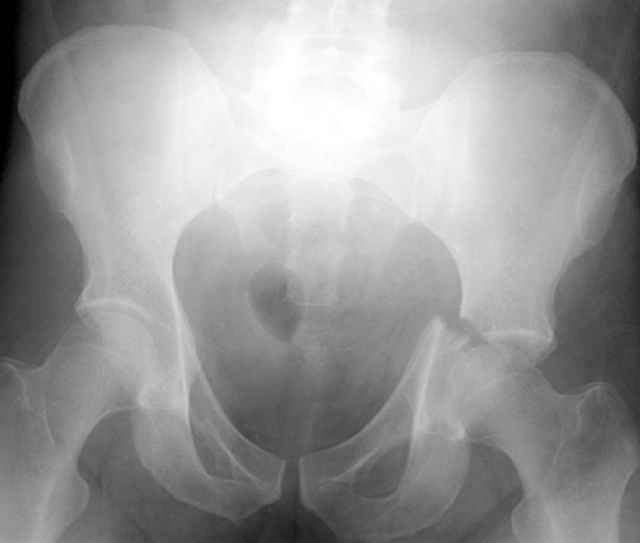

45 yo male in MVA, only other injury=small subarrachnoid bleed (neurologically fine, GCS never <14), with this transverse & associated posterior wall fx-dislocation 7/7

Pt has a history of prior abdominal surgery in Colombia (gastric bypass for obesity -- now <200 lbs).

In skeletal traction thru distal femoral pin 40 lbs with decent reduction - except for the free fragments in the hip joint. ORIF planned for post-injury day 11.

the case that I found is a 20yo male, MCC. his AP pelvis shows an interesting position of his bladder. it is pushed aside by a hematoma from SGA injury. we did a limited lateral window approach for the anterior column first, pt bumped up/supine. then closed and repositioned for KL. I could not find intra-op photos of cases when we did only a small incision for the AC screw (but they do exist!!). the lateral window is available for reduction assessment if a KL approach is being used. in the lateral position this window is available. the prone position definitely takes pressure off of the post column and facilitates reduction. in the lateral position a schantz pin in the ischial tub +/- bone hook in sciatic notch helps with PC reduction. the lateral position also gives better airway access for anesthesia. airway problems are rare, but prone position seems to be a bit more of a challenge to exchange the tube, or reintubate altogether. just something further to debate!